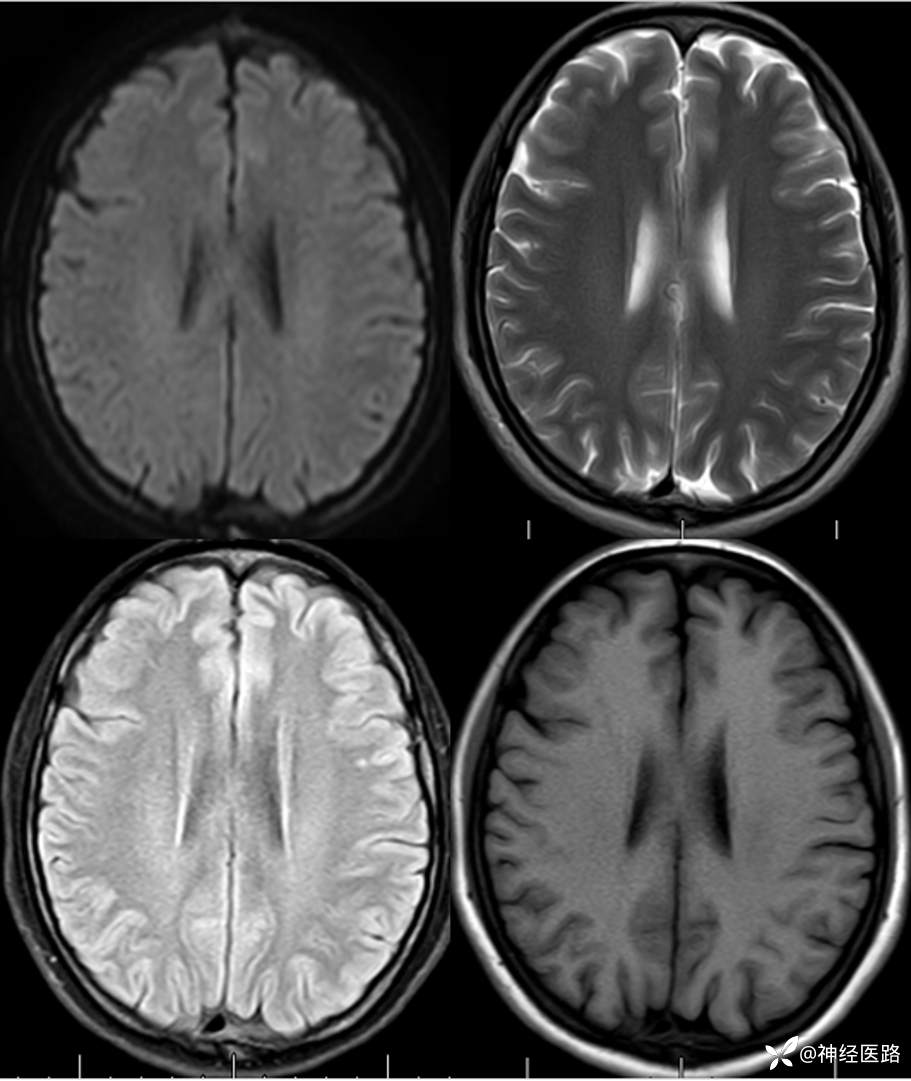

辅助检查:头部磁共振: 1.左侧额叶及右侧顶叶白质内高信号,请结合临床及相关检查。2.双侧小脑半球脑萎缩。3.部分颅骨信号增高。